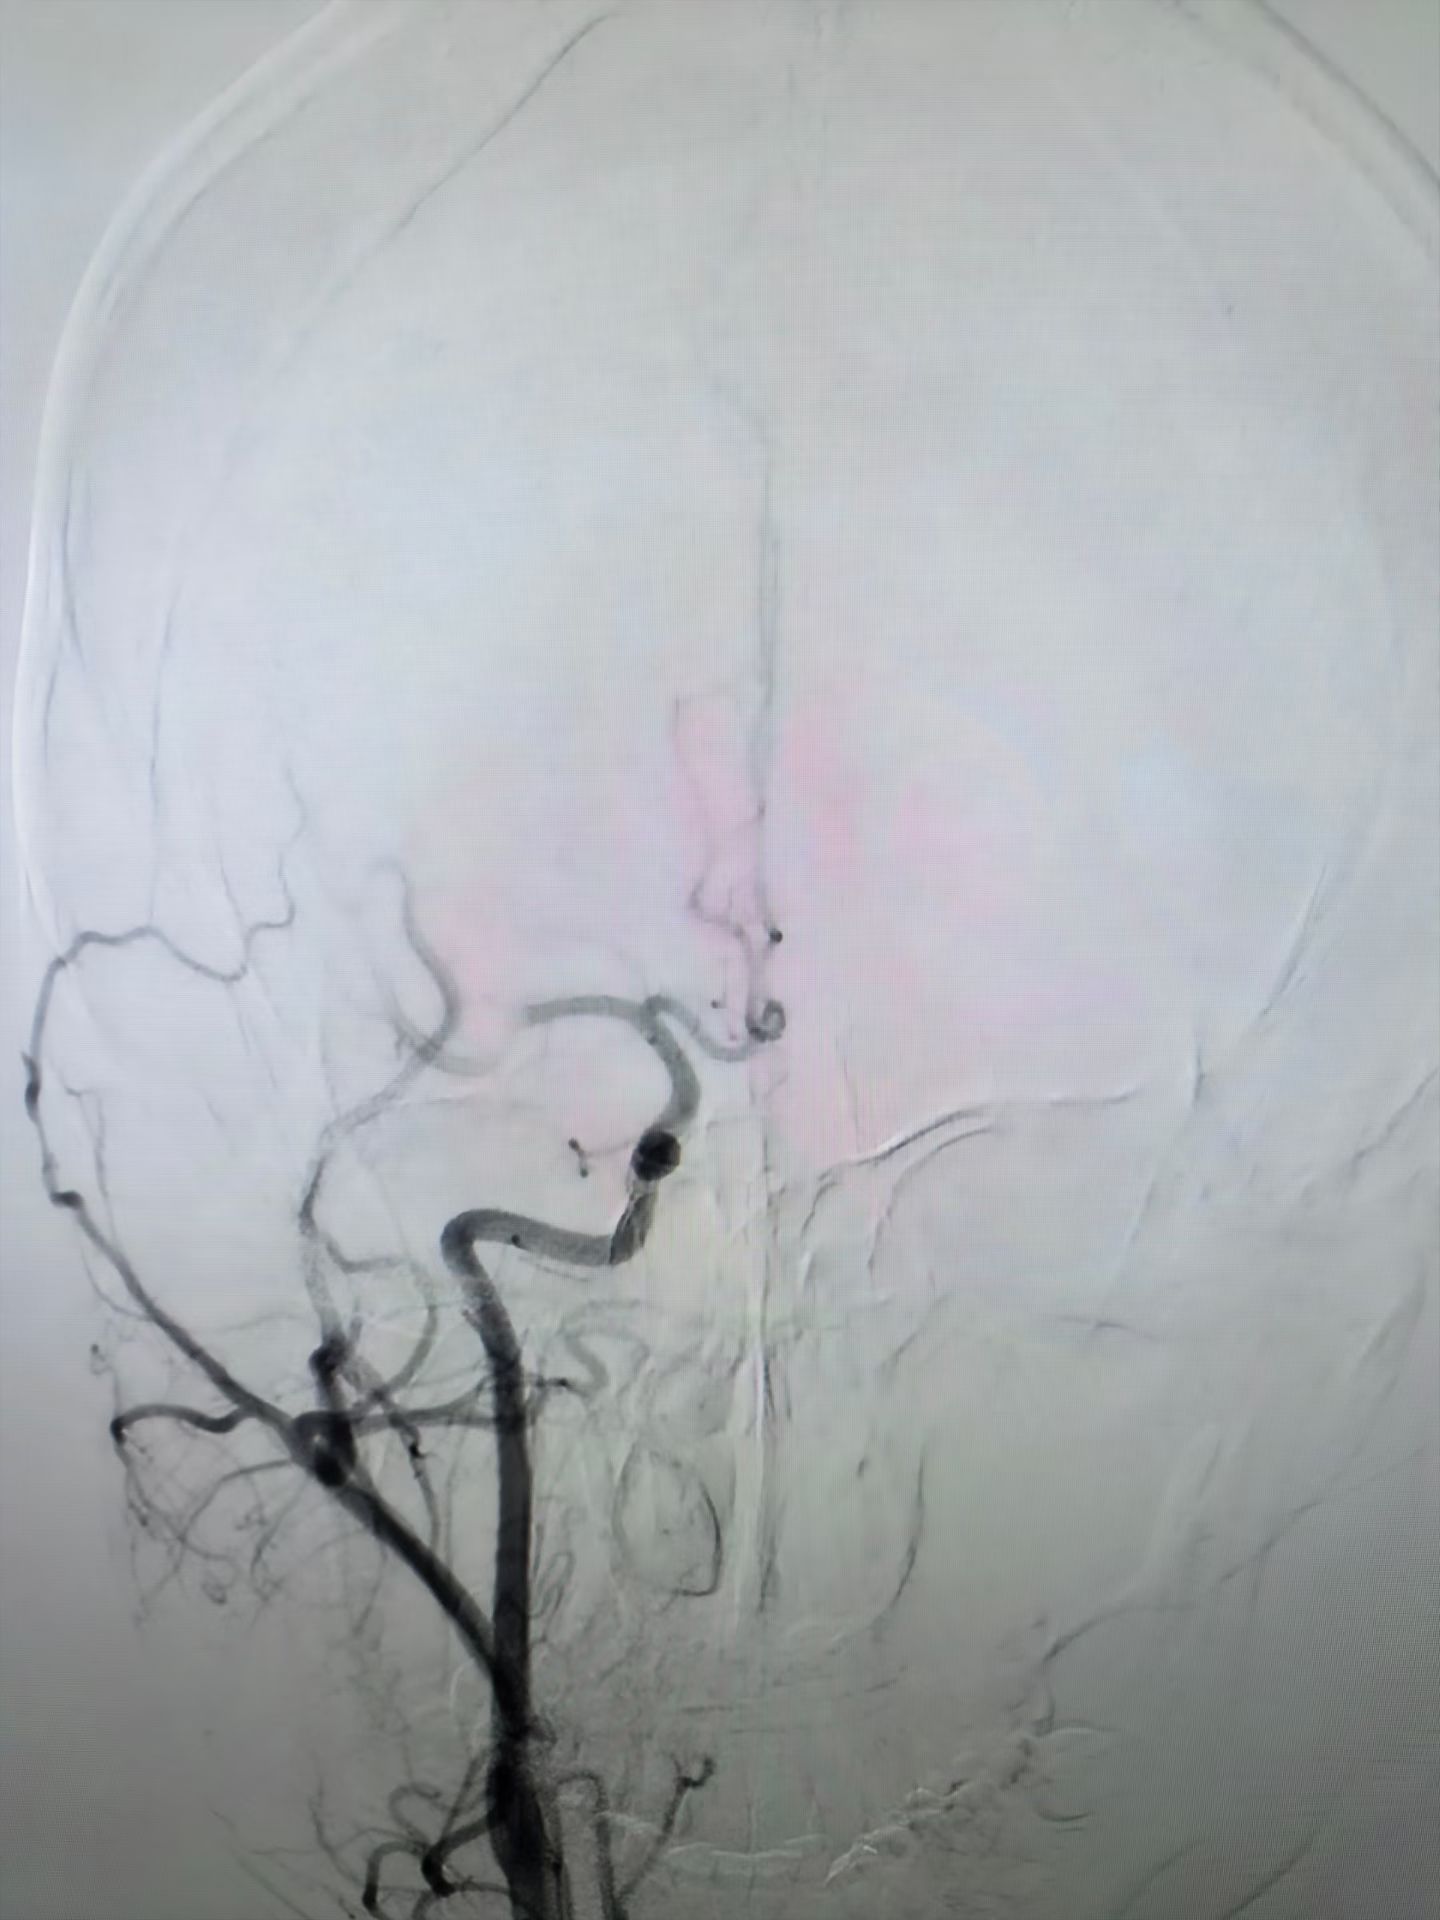

介入中心